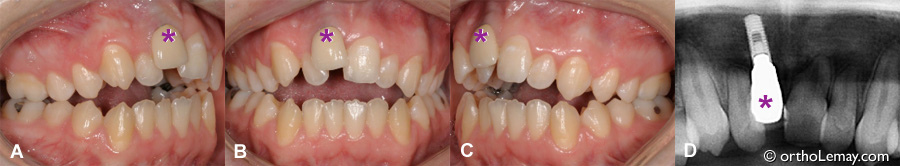

Implant dentaire posé chez un adolescent (12 ans) et contribuant au développement d’une malocclusion importante avec la croissance résiduelle.

(A, B, C) À l’age de 17 ans, soit 5 ans après la pose de l’implant dentaire, un importante béance antérieure et constriction maxillaire (occlusion croisée) se sont développées. Initialement, toutes les dents antérieures étaient en contact. La couronne (*) implanto-portée n’a pas bougé tandis que les autres dents ont migré verticalement et vers l’intérieur créant cette importante malocclusion.

(D) Radiographie montrant le niveau de l’implant (*) par rapport aux autres dents.

Un tel implant ne peut être déplacé en orthodontie et il devra être retiré et remplacé ultérieurement une fois les corrections orthodontiques terminées.